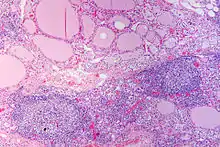

En microscopie les lésions consistent en une association de fibrose interstitielle, d'infiltration lymphoïde et de destruction épithéliale[1],[2]. Le degré de fibrose est très variable[1]. L'infiltration lymphoïde présente une organisation en follicules avec des lymphocytes B au centre et des lymphocytes T dans le cortex[2]. Les cellules épithéliales thyroïdiennes sont également modifiées, apparaissant élargies et acidophiles (cellules de Hürthle)[2].